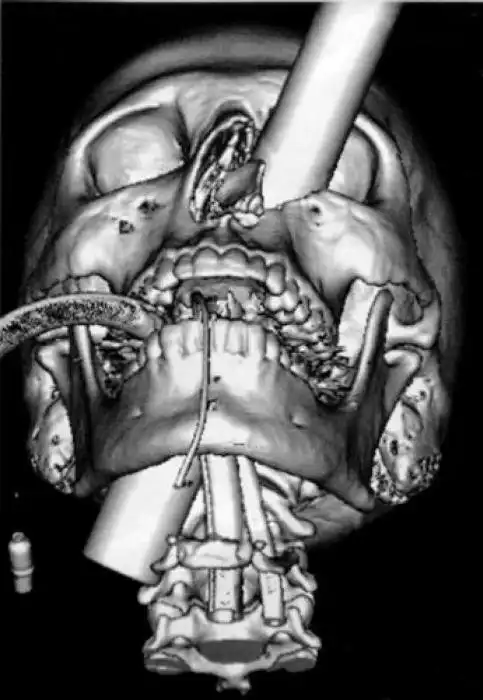

На рентгеновских снимках людей порой можно обнаружить самые необычные предметы, которые находятся в их теле.